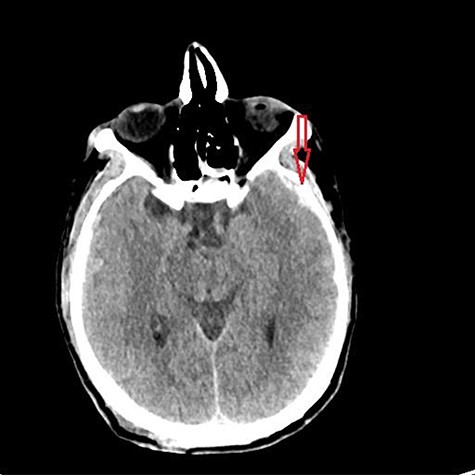

He had a significant recovery, to the point where he was awake with mild right paresis. He was following commands briskly but remained nonverbal. On hospital day 26, he developed neurological deterioration with decreased mental status and worsening right hemiparesis. Clinical examination noted pronounced new indentation of his hemicraniectomy flap site. CT head showed a rightward shift away from the craniectomy site and impending herniation (Fig. 4).

CT head POD26 from craniectomy demonstrating findings consistent with SSFS.